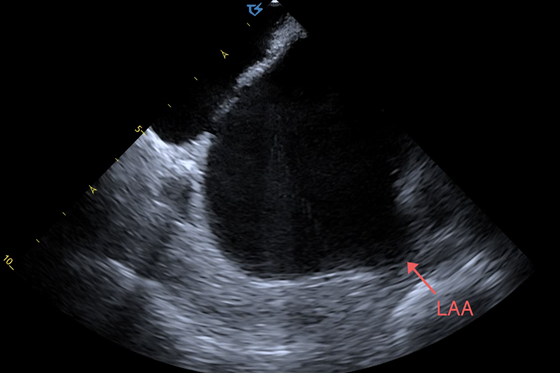

60岁的李大叔4年前来湘雅常德医院检查冠脉造影和心脏彩超均未发现异常,今年李大叔来医院进行复查,检查发现李大叔的心脏彩超双房偏大,心脏收缩功能较前下降明显。医疗人员为减轻患者症状及延缓心衰,建议患者及家属行射频消融术,反复告知其手术的成功率及手术相关风险后,患者和家属同意行射频消融术。术前需常规完善食道超声排除左房及左心耳血栓,经反复尝试患者完全不能耐受食道超声检查,但患者及家属手术意愿强烈,心血管内科主任彭道地、副主任医师杨国栋、主治医师龚辉、主治医师彭双进行反复讨论,考虑可行心腔内超声检查,若排除血栓,再继续行ICE指导下射频消融术。9月26日,完善术前准备后,手术团队首先为患者行心腔内超声检查,未见左房及左心耳血栓形成,决定继续为患者实施射频消融术,经过2小时精心手术,手术成功。术后,李大叔恢复窦性心律,术后继续药物治疗。

据彭道地教授介绍,心腔内超声心动图( ICE)指在导管的顶端安置超声探头,经由外周血管输送至心腔内部,对心脏及其邻近组织进行实时高质量成像和(或)血流动力学测定的超声成像技术。ICE能够直接显示心脏结构,有助于理解心脏内各部位之间的解剖关系,现已逐渐推广应用于指导各种心脏介入手术、监测术中相关并发症,是各种心脏介入手术中重要的辅助工具。

房颤射频消融术之前需常规排除左心房及左心耳血栓,食道超声(TEE)一直是传统的房颤导管消融或左心耳封堵术前排除左房及左心耳血栓的金标准,且价格实惠,但TEE会给患者带来更多不适,检查前需要禁食禁水,检查时需要患者配合,检查中还可能会引起食管损伤。左房CTA也用于左心耳血栓的诊断,但由于需要丰富的诊断经验、假阳性率较高,以及需要静脉注射对比剂等因素未能广泛应用。与TEE相比,ICE价格虽较为昂贵,但患者不适感较少,配合度高,且可指导后续手术过程,降低并发症发生率并减少射线量。针对左房及左心耳血栓,已有诸多临床研究表明,ICE临床应用价值不亚于TEE。